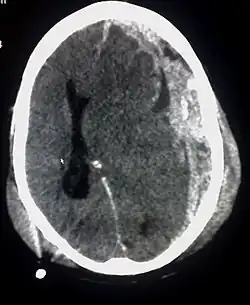

Subduralhämatom

Als Subduralhämatom oder subdurales Hämatom (SDH) wird ein durch Verletzung von Venen entstandener Bluterguss (Hämatom) unter (lateinisch sub) der harten Hirnhaut (lateinisch Dura) zwischen Dura mater und Arachnoidea bezeichnet.

Das akute subdurale Hämatom tritt bei schweren Schädelverletzungen begleitend mit weiteren Schäden auf. Es muss bei entsprechender Größe und Dynamik unter Öffnung des Schädels (Trepanation) entlastet werden und endet ohne Operation, insbesondere bei bestehender Mittellinienverlagerung,[8] meist tödlich.

Das chronische Subduralhämatom oder chronische subdurale Hämatom entsteht typischerweise durch leichte Schädel-Hirn-Traumata, definitionsgemäß nach mindestens zwei Wochen,[9] wobei meist (in 50 Prozent der Fälle) bei Exploration kein Trauma zu eruieren ist. Hohes Alter und Gerinnungshemmung (durch Medikamente oder alkoholische Leberschädigung) begünstigen seine Entstehung. Bei älteren Menschen kommt es zu einer physiologischen Hirnvolumenminderung und somit zu einem Zug an den Brückenvenen, die dann durch leichte Traumen beschädigt werden können. Der Abfluss des Blutes über besagte Brückenvenen kann durch das Subduralhämatom behindert werden, so dass es zusätzlich zu einer venösen Kongestion des Hirnteiles kommt, über dem das Subduralhämatom liegt. Kopfschmerzen, Druckgefühl, Desorientierung, Bewusstseinsstörung, aber selten auch Lähmungen, insbesondere Halbseitenlähmungen,[10] können die Folge sein. Auch das chronische Subduralhämatom wird nach außen drainiert, hier ist die Prognose besser als beim akuten.